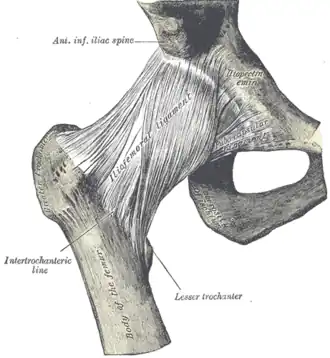

Right hip-joint from the front

Right hip-joint from the front -